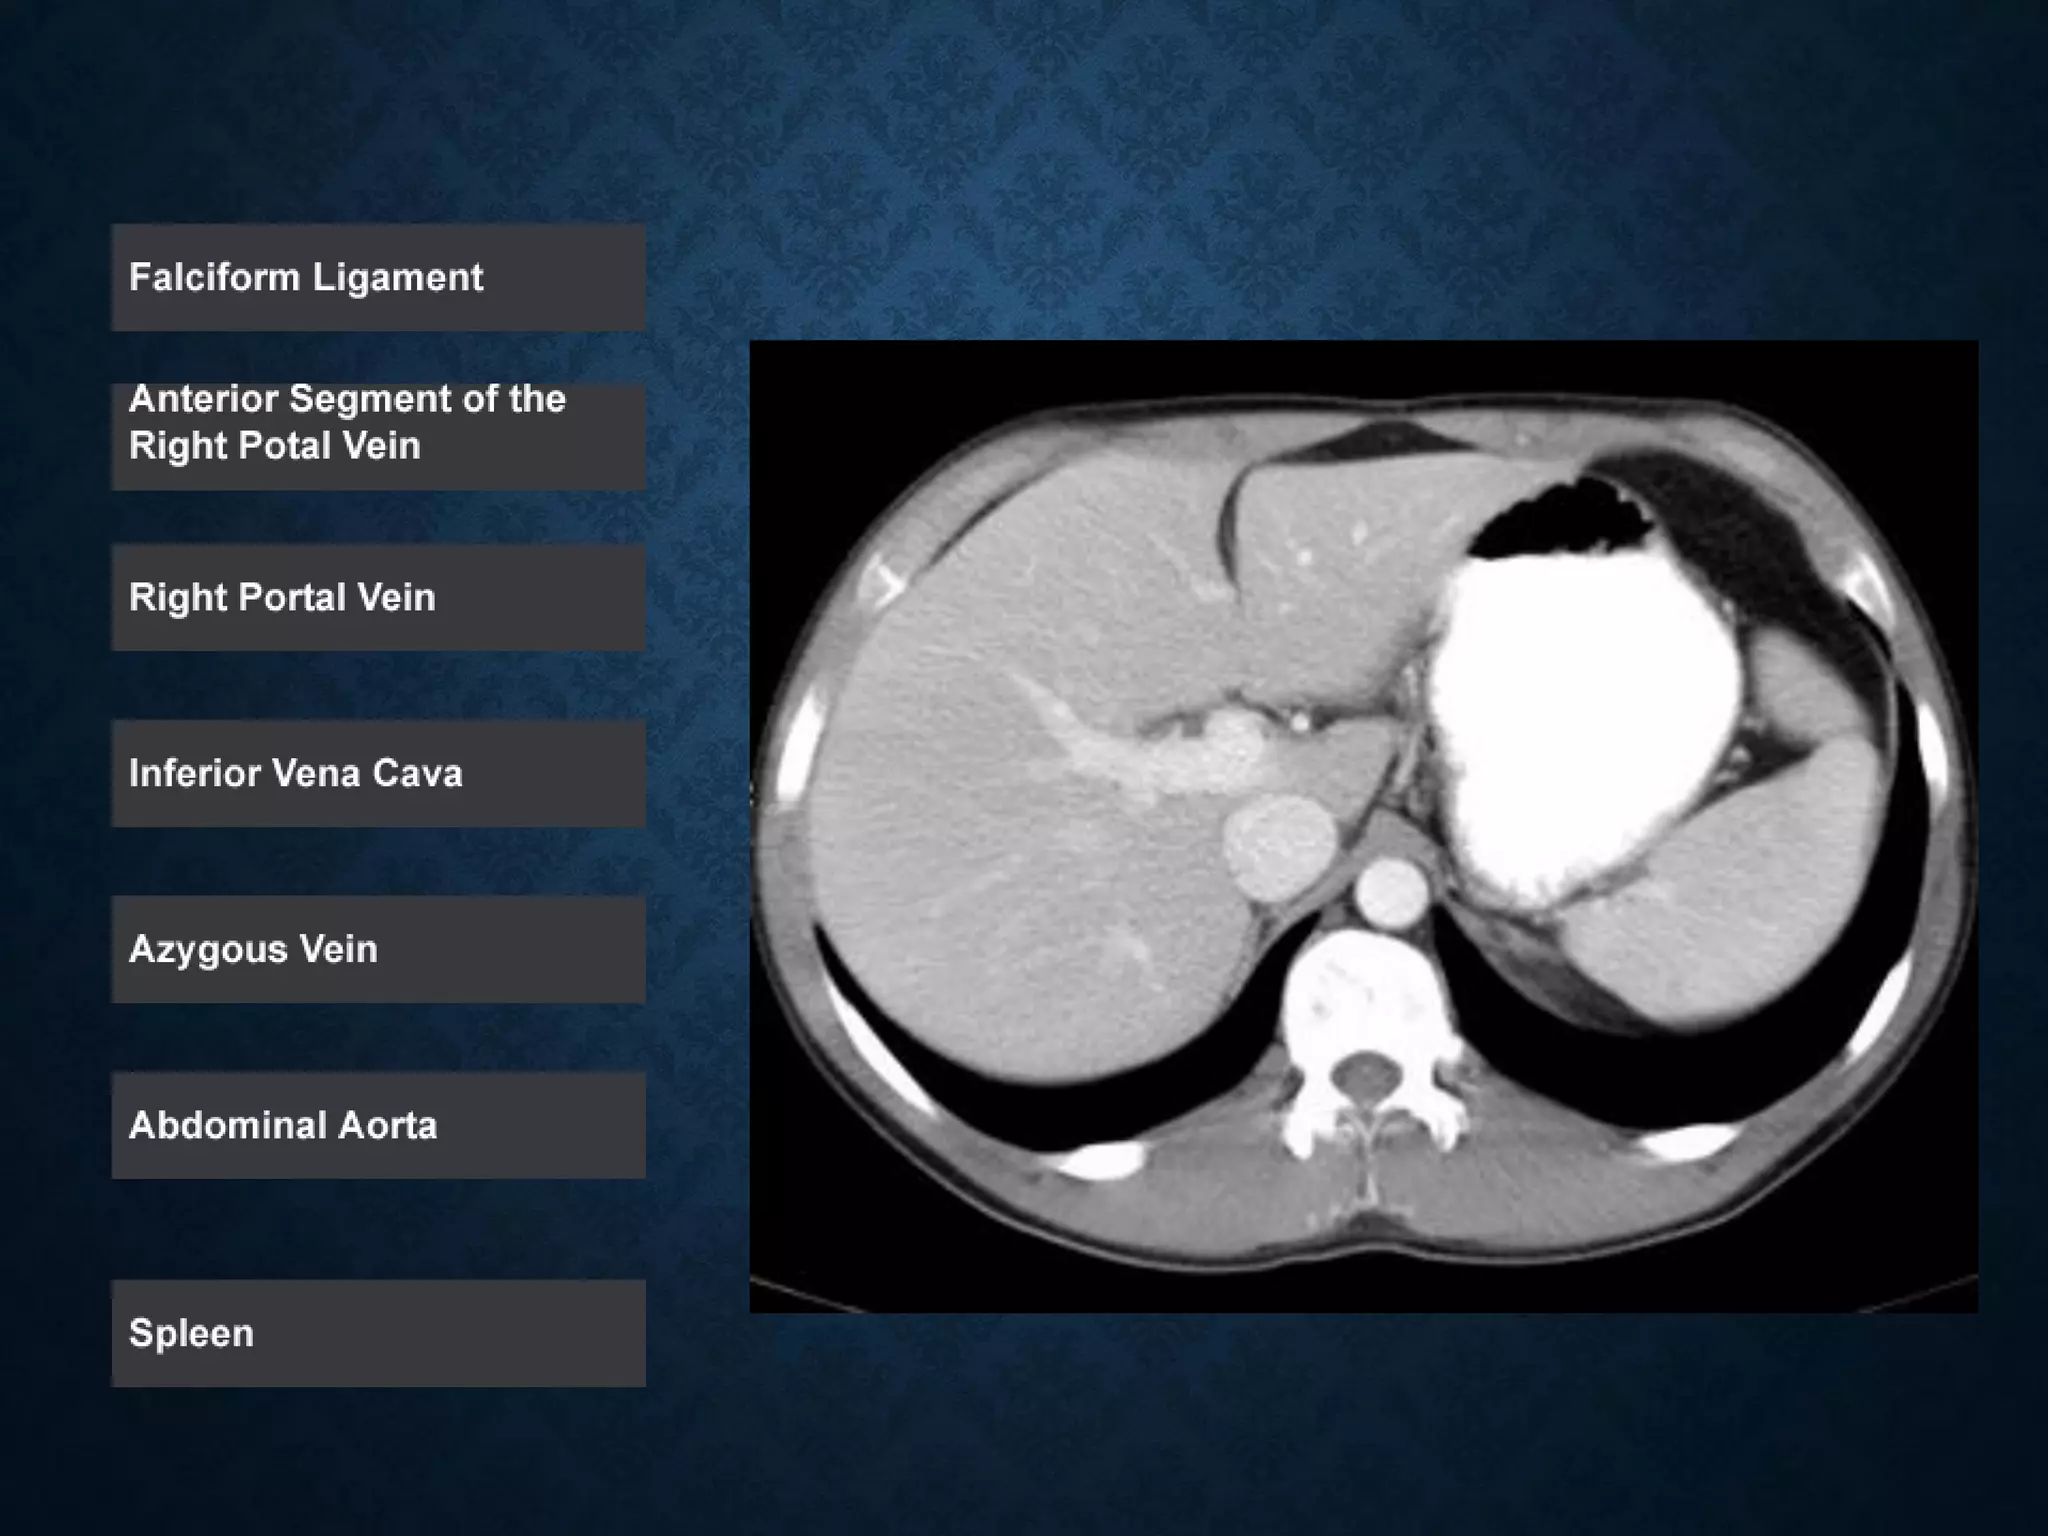

ABDOMINAL AORTA

origin: Continuation of descending thoracic aorta at T12

• course: descends anterior and slightly to the left of the lumbar vertebral

bodies.

•Bifurcation of aorta:L4

• Note that the bifurcation (union) of the inferior vena cava is at L5and

therefore below that of the bifurcation of the aorta)

ABDOMINAL AORTA origin: Continuationof descending thoracic aorta at T12 • course: descends anterior and slightly to the left of the lumbar vertebral bodies. •Bifurcation of aorta:L4 • Note that the bifurcation (union) of the inferior vena cava is at L5and therefore below that of the bifurcation of the aorta)